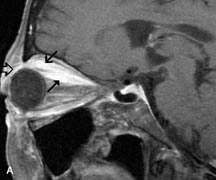

MRI is particularly helpful in the detection and characterization of subperiosteal hematomas of the orbit (Fig. 19). They are most commonly seen in the subperiosteal space of the superior orbit as well-defined masses following a traumatic injury. The signal intensity varies depending on the acute, subacute, or chronic nature of the hematoma, based on the stage of blood degradation. Fresh hemorrhages are hypointense on T1-weighted images and hyperintense on T2 images. Hematomas that are 1 to 7 days old are hypointense on both T1- and T2-weighted images. T1-weighted images of hematomas more than a week old are hyperintense due to the oxidation of deoxyhemoglobin to methemoglobin, whereas the T2 images remain hypointense.63

Fig. 19. A. T1- and (B) T2-weighted MR scans demonstrate a large acute subperiosteal hematoma (H) that lies between the cortical bone of the orbital roof and the inferiorly displaced periorthira (double arrow). The extracopal fat (arrow) and levator muscle are displaced inferiorly.